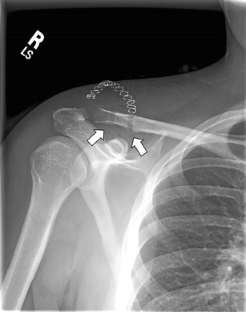

Fig. 2